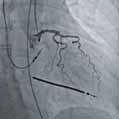

Доступна діагностика - це ангіографічна система Alphenix Core+

Ангіогафічна система Alphenix Core+ від Canon Medical є базовою у своєму роді. Її надійність підкріплюється надзвичайно потужним рівнем візуалізації. Завдяки Alphenix Core+ ви матимете змогу проводити якісні інтервенційні процедури, із можливістю постійно покращувати рівень діагностики. Зумовлено це можливістю розширювати її конфігурації.

Новий рівень візуалізації

Для закладів, що прагнуть досягти більшого за менших витрат, найкращим вибором стане ангіограф Alphenix Core+. Ця система повністю відповідає сучасним вимогам до проведення інтервенційних процедур із можливістю розширення конфігурації в майбутньому.

• Цифрова субтракційна ангіографія (DSA);

• Режим роботи Roadmap;